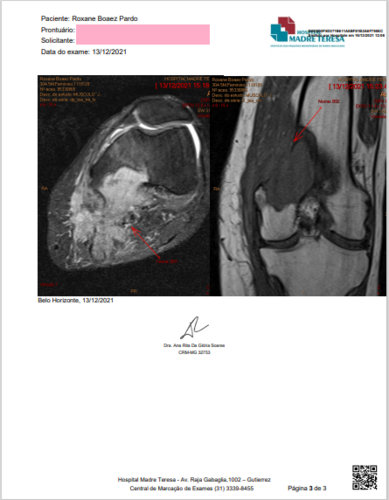

Vou te contar um pouco da minha história… logo no inicio da pandemia tratando um outro tumor benigno descobri o segundo tumor que apos 3 biopsias confirmaram fasciite nodular e em novembro de 2020 retirei o então tumor benigno e estava de férias do bisturi e rumo a vida normal porém esse tumor benigno escondia um Câncer raro no osso (sarcoma miofibroblástico de baixo grau) … Apesar do diagnóstico que ninguém gostaria de ter me sinto grata por ser um tumor que não costuma se espalhar tão rápido e pelas pessoas que tenho do meu lado e as tantas que já me ajudaram a arrecadar o valor da cirurgia de amputação em tempo recorde <3

Me chamo Roxane Pardo, sou natural de Rio grande - RS e criei essa vakinha com intuito de arrecadar fundos para fazer cirurgia de preservação de membro01/06/2021 - Hoje recebi a noticia que existe a possibilidade de me curar da doença sem precisar amputar, para isso preciso pagar os custos com honorarios medicos e custos com pos operatório, além de seguir com tratamento metabolico que vem dando certo ate hoje.19/12/2021 - Por ter sido considerada no Rio grande do Sul, como “terminal” e sem nenhum tratamento que fosse resolver o problema, procurei por medicos fora e desde entao estou morando em BH, hoje meu processo todo iniciou do zero, pois os laudos que apresentei nao estavam tao precisos, ou seja ficarei aqui em BH até o fim do tratamento que ainda nao sabemos qual é.